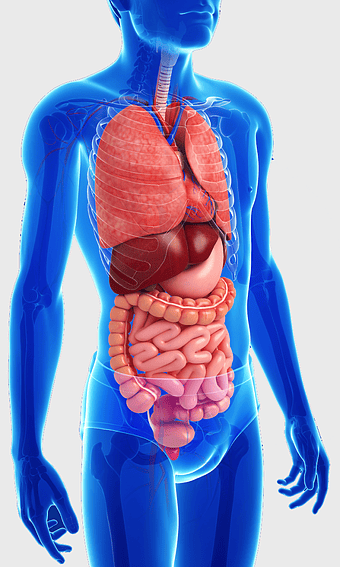

Pulmonary pleurae, Lung Tuberculosis, Pleural cavity, respiratory system, lung anatomy, medical illustration, pulmonary health, PNG

- respiratory system

- lung anatomy

- medical illustration

human stomach anatomy, gastrointestinal tract illustration, digestive system organ, abdominal cavity viscus, internal organ diagram, medical biology graphic, human body internal structure -

human gastrointestinal tract anatomy, human digestive system illustration, gastrointestinal disease symptoms, human body organ diagram, internal organ visualization, medical anatomy study, digestive health awareness -

human digestive system, gastrointestinal tract anatomy, liver function, stomach and intestines, digestive health, internal organs diagram, human body systems -